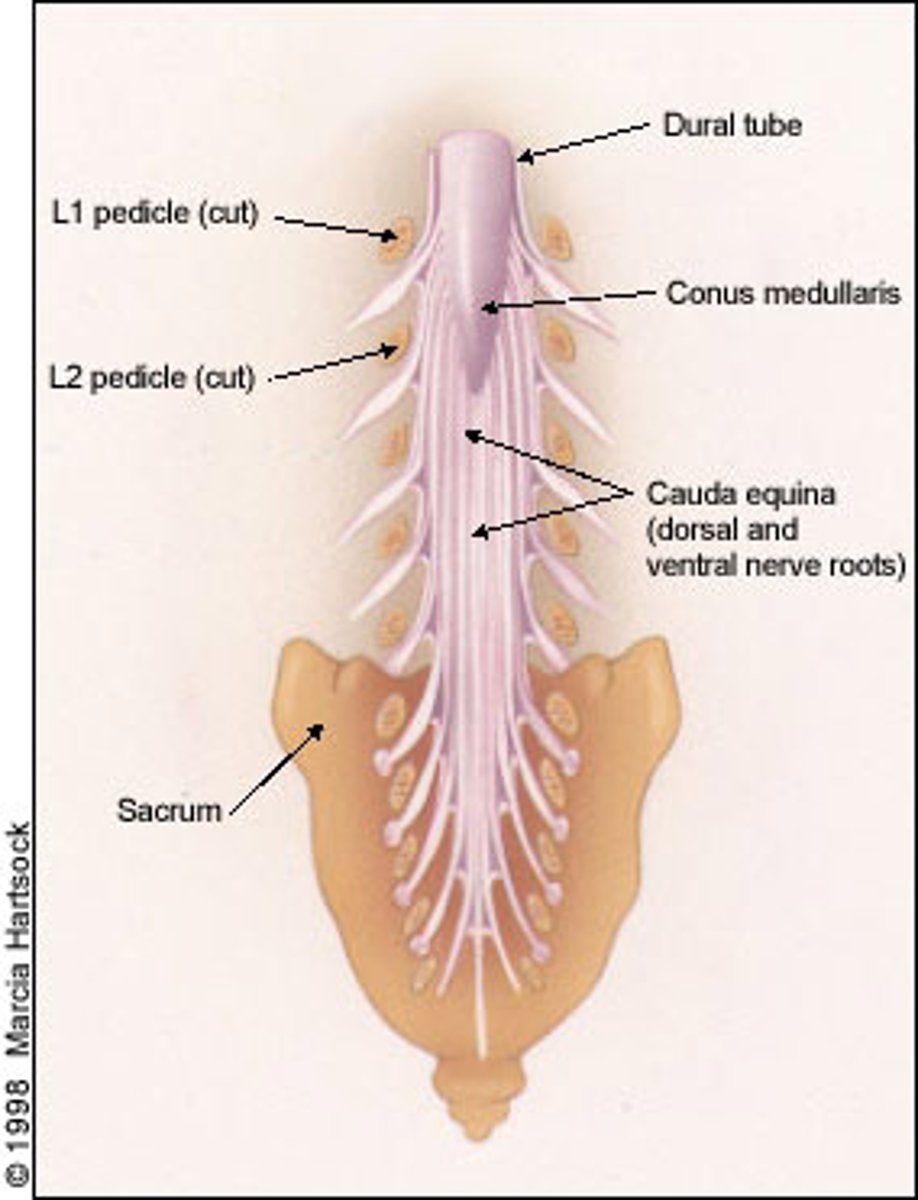

conus medullaris

Cone shaped end of spinal cord at L1-L2

cauda equina

Nerve roots from spinal cord to lower intervertebral foramen to exit

L2 to S5 and filum terminale

filum terminale

anchors the spinal cord to the coccyx and sacrum

Pia mater

terminal thread